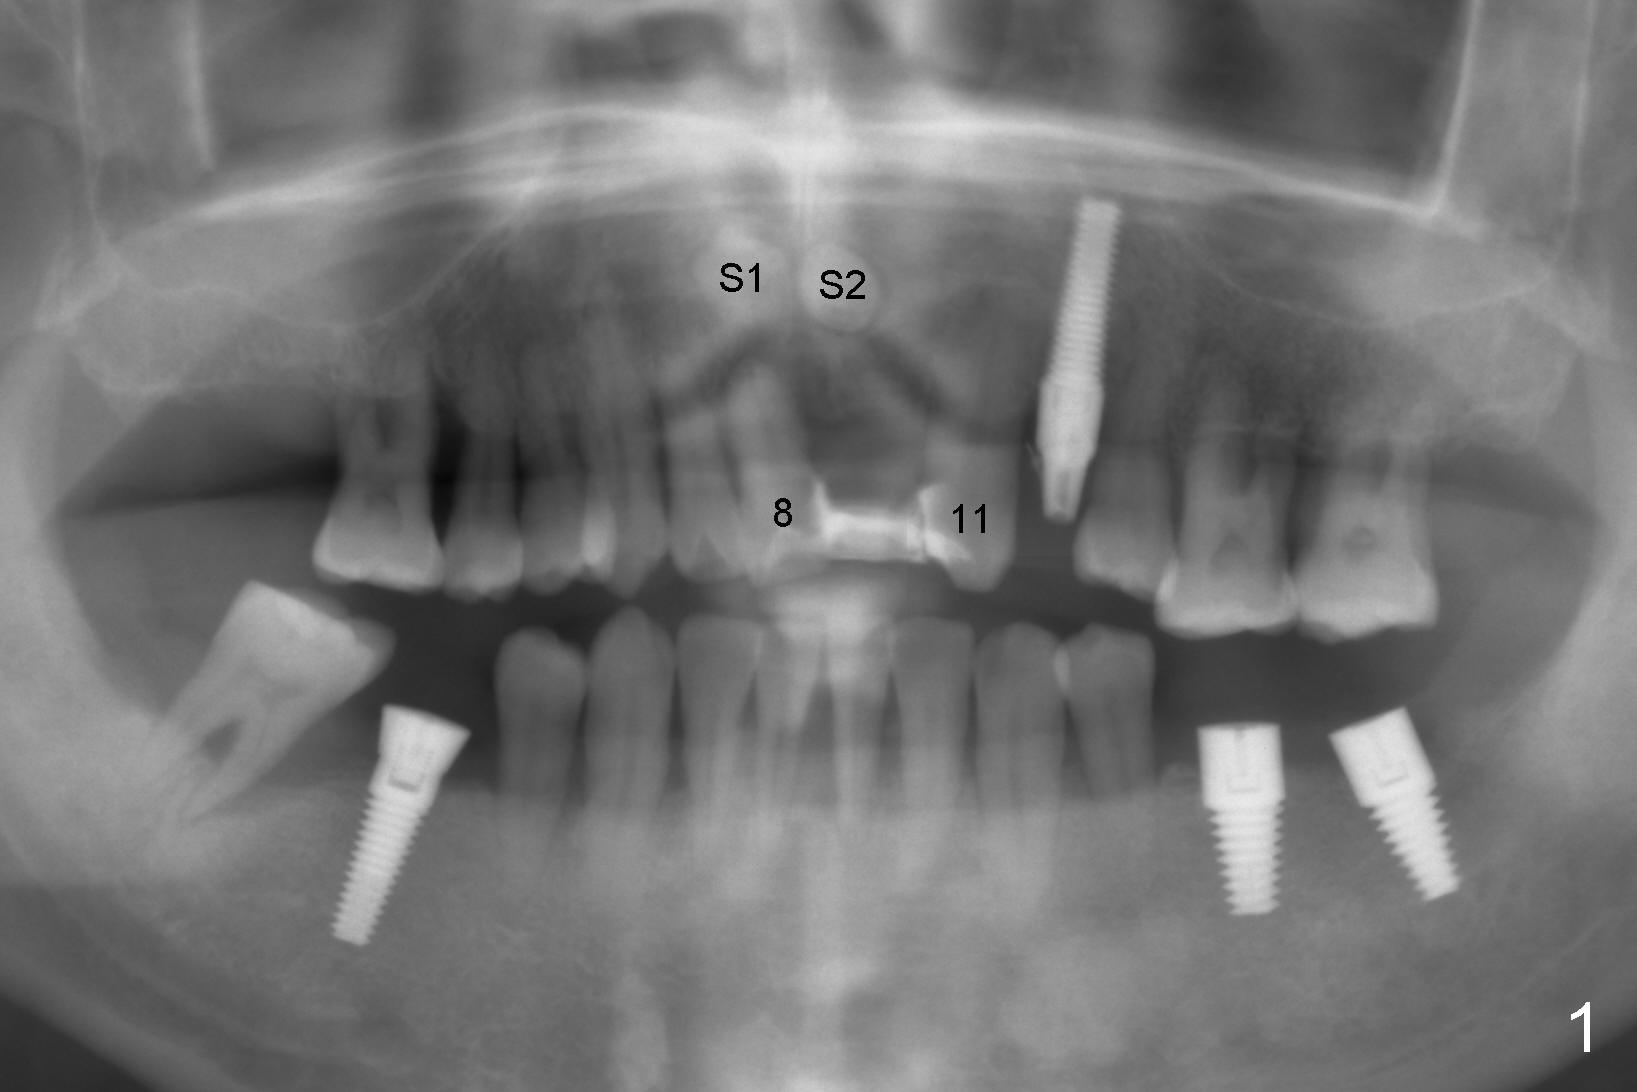

A 41-year-old man has poor dentition (Fig.1: #12 immediate provisional). It appears that #10 is congenitally missing. A temporary bridge is fabricated (Fig.1: #8-11) when #9 is reportedly extracted. Recently bonding between #9 pontic and #11 detaches. The bridge is loose (Fig.2). The tooth #8 is periodontally compromised (Fig.3,5: CT sagittal and coronal sections, respectively).

Treatment plan is to extract two supernumerary teeth (S1,S2) and #8, bone graft (mainly S1,2 sockets, and #8 buccal for cosmetics) and place immediate implants at the sites of #8 and 9. Long implants (20 mm) are to be used to engage into the two bone segments, coronal and apical to the S1,2 sockets (Fig.5,6). Since the bone segment apical S1,2 sockets is mainly cortical (arrowheads in Fig.3-6; lamina dura and nasopalatine canal), the two implants are expected to be stable. A palatal incision is going to be made to expose S1,2, as one of them (S2) is more or less palatal (Fig.6). Here is surgery.